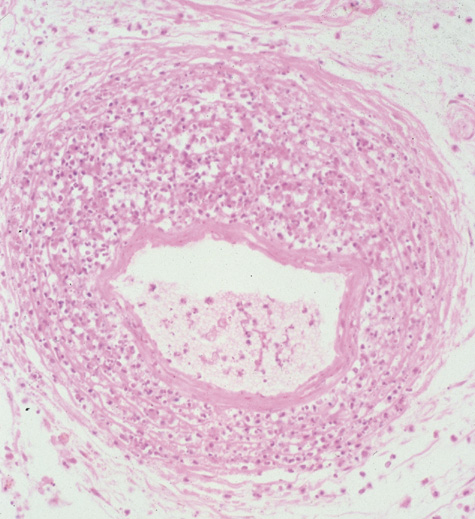

Biopsy of tissue within the orbit shows invasion of the mucosa, submucosa, and bone in cases of invasive fungal sinusitis or a granulomatous reaction without mucosal or bone invasion in the noninvasive form. The material within the sinuses may be yellowish, black, or friable. Hyphae are not seen within the mucosa or bone of patients with the noninvasive form but can be seen on routine stains of mucus. Multiple specimens should be examined116 in a search for septate fungal hyphae of relatively uniform width that are apparent on hematoxylin and eosin staining.

Diagnosis is made by having a large index of suspicion and obtaining specimens of nasal turbinate, sinus, or infected orbital tissue. Large, branching nonseptate hyphae are readily apparent on hematoxylin and eosin staining or with methenamine silver staining (see Fig. 23). These hyphae can be grown on fungal culture.